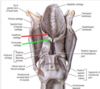

list the three parts of the pahrynx

- pharynx

- three parts

- nasopharynx

- lies above the soft palate

- oropharynx

- extends from the soft palate to the upper border of the epiglottis

- lies behind the oral cavity

- laryngopharynx

- extends from the upper border of the epiglottis to the lower border of the cricoid cartilage, where it is continuous with the esophagus.

- lies behind the aperture and posterior wall of the larynx

are depressions within the laryngopharynx on each side of the larngeal inlet and the lateral wall of the larynx

- piriform recesses (priform fossae)

- are depressions within the laryngopharynx on each side of the larngeal inlet and the lateral wall of the larynx

- are sites where food or foreign objectts may become lodged and may damage the internal laryngeal nerve lying just deep to the mucous membran

- attempts to remove foreign objects also may damage the nerve

- the nerve may be anestetized for endo tracheal intubation